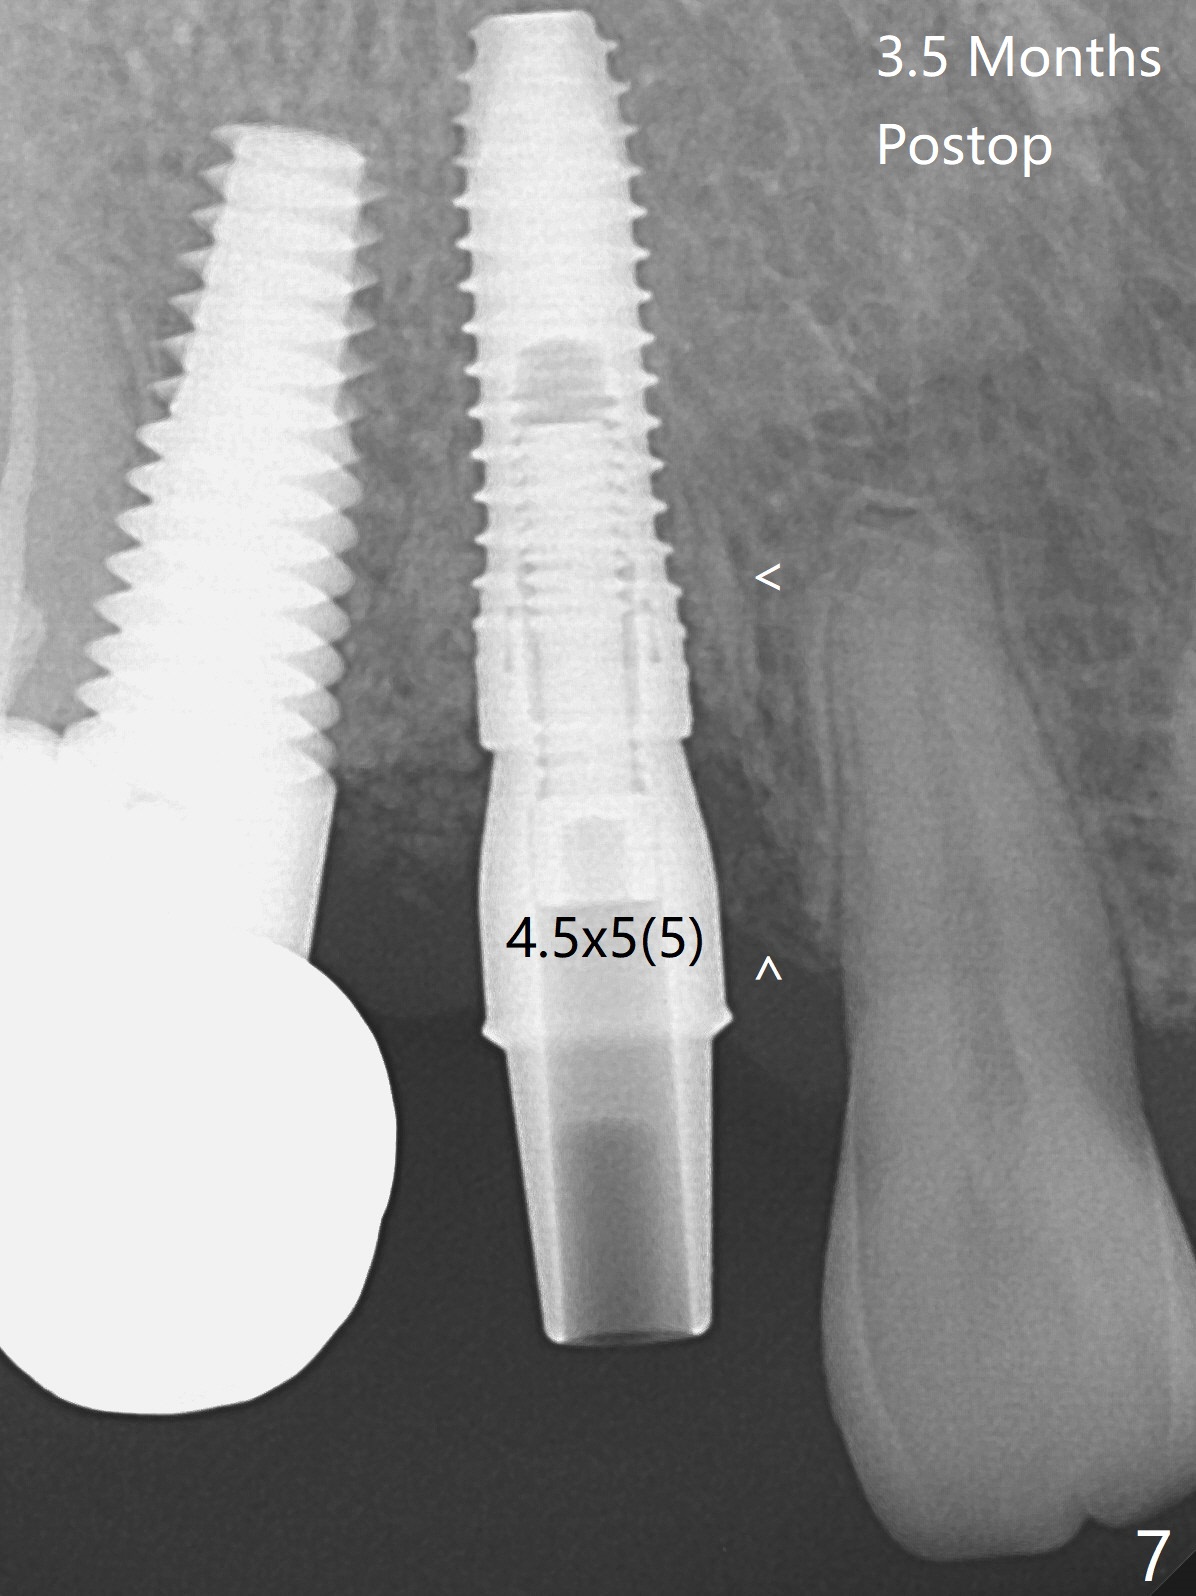

When the recemented crown at #6 is removed, the post is found to have been fractured. When the tooth is extracted, the socket walls are found intact. After moving the initial osteotomy (Fig.1) mesial, a 3.8x13 mm implant is placed (Fig.2). Clinically it appears supracrestal lingually. So the implant is placed deeper, but a cemented abutment is incompletely seated (Fig.3 <). When a longer abutment is used (easy grasping), it is seated completely (Fig.4). Then sticky bone is packed (Fig.5 *). When an immediate provisional is fabricated and seated, PRF membranes are inserted into the remaining gap between the gingiva and the provisional. Free hand surgery takes time and more intraop X-ray. It is inconvenient with nervous patients. The socket heals 2 weeks postop (Fig.6). The provisional will be next relined and reseated. It is difficult to insert gingival retraction cord 3.5 months postop because of the deep mesial margin. When an abutment with longer cuff is placed, the packing is easier (no biologic width violation, Fig.7 (^: resorbed mesial crest), as compared to Fig.5). When the crown is cemented (un-esthetic due to failure of use of temporary abutment), the metal shows at #5 with gingival recession because of buccal placement (Fig.8-10). Bone resorption is severe between #5 and 6 (Fig.7), as related to large gingival embrasure (Fig.9 *). When #5 crow is redone, move the gingival margin apical and fabricate provisional.